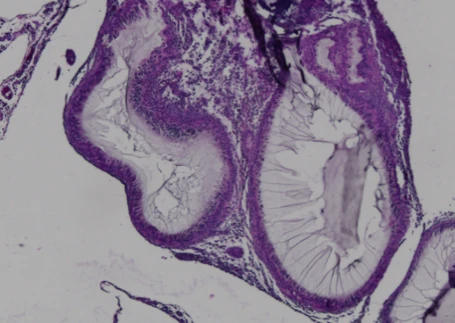

Cells encapsulated in CSS® hydrogel remain viable with minimal immune infiltration. The surrounding tissue shows healthy integration without fibrosis, demonstrating sustained protection and function

- Histological analysis: tissue response vs untreated controls (e.g., immune rejection vs CSS®-encapsulated delivery, as shown in Likarda data).